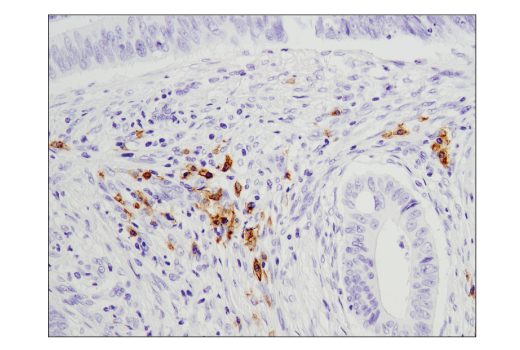

Immunohistochemical analysis of paraffin-embedded human endometrioid carcinoma using CD19 (Intracellular Domain) (D4V4B) XP® Rabbit mAb performed on the Leica® Bond™ Rx. Data were generated using the standard formulation of this product.

Immunohistochemistry Image 1: CD19 (Intracellular Domain) (D4V4B) Rabbit Monoclonal Antibody (BSA and Azide Free)